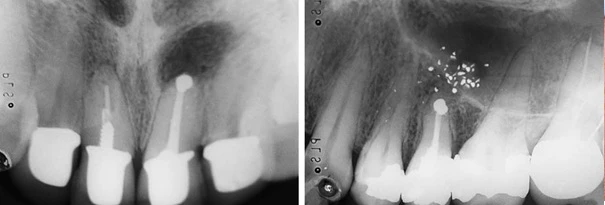

Hình ảnh X quang cho thấy nang quanh chóp răng cửa giữa mà nguyên nhân do điều trị nội nha chưa tốt. Chưa xuất hiện hình ảnh lỗ rò trên lâm sàng.

Hình ảnh so sánh một ca cắt chóp trám ngược tốt với chất trám bít kín chóp răng và một trường hợp để rơi chất trám ra mô quanh chóp.